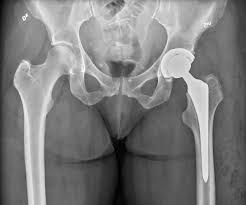

Hip Replacement in Lahore: A Comprehensive Guide for 2025

Hip replacement surgery is a life-changing procedure that helps individuals suffering from chronic hip pain caused by conditions like arthritis, fractures, or other joint disorders. This surgery involves replacing a damaged hip joint with an artificial one, providing pain relief and restoring mobility. If you’re considering Hip Replacement in Lahore, Orthocenter is one of the […]